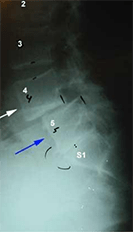

Self-verified p. Awesome Doctor. Dr. Hannani is a straight forward and down to earth surgeon. He explained my condition and my options very clearly. He and his entire staff are friendly and accommodating. My spine was slipping at S1-L5 and pinching my sciatic nerve. After the surgery the pain was immediately gone. The hospital staff were amazing. I had meet with another surgeon and reviewed at least 20 others. After meeting with Doctor Hannani I felt confident I would not find anyone more focused in his profession. Or in who's care I would be better treated. - 2/28/2017

Gregory E. Dr. Hannani is a straight forward and down to earth surgeon. He explained my condition and my options very clearly. He and his entire staff are friendly and accommodating. My spine was slipping at S1-L5 and pinching my sciatic nerve. After the surgery the pain was immediately gone. The hospital staff were amazing. I had meet with another surgeon and reviewed at least 20 others. After meeting with Doctor Hannani I felt confident I would not find anyone more focused in his profession. Or in who's care I would be better treated. - 11/30/2017

Gregory E. Dr. Hannani is a straight forward and down to earth surgeon. He explained my condition and my options very clearly. He and his entire staff are friendly and accommodating. My spine was slipping at S1-L5 and pinching my sciatic nerve. After the surgery the pain was immediately gone. The hospital staff were amazing. I had meet with another surgeon and reviewed at least 20 others. After meeting with Doctor Hannani I felt confident I would not find anyone more focused in his profession. Or in who's care I would be better treated. - 7/01/2019

Patient February 28th, 2017 Dr. Hannani is a straight forward and down to earth surgeon. He explained my condition and my options very clearly. He and his entire staff are friendly and accommodating. My spine was slipping at S1-L5 and pinching my sciatic nerve. After the surgery the pain was immediately gone. The hospital staff were amazing. I had meet with another surgeon and reviewed at least 20 others. After meeting with Doctor Hannani I felt confident I would not find anyone more focused in his profession. Or in who's care I would be better treated. - 2/28/2017

Brandon T. So I’ll start my review by saying my back was pretty messed up. I herniated my L5 and it was crushing my S1 nerve root causing the worst Sciatica pain I’ve ever experienced in my life. It was such a blessing that I found Dr Hannani. The staff he has working for him at his office are all friendly and they answer any questions you made have. I spoke with Eddie who helped me with all my appointments and answered all my questions and concerns prior to surgery. From the first visit I had with Dr. Hannani I felt confident. He explained my whole situation and showed me what needed to be done from looking at my MRI. We requested surgery and I was approved through my workers comp. the process before surgery was easy and the Queen of the Valley hospital took care of me ! I am SO HAPPY that was able to have all of this done and even MORE HAPPY that I was under the care of Dr. Hannani. MY SCIATICA IS GONE. I’ve dealt with this injury for over a year and 8 months. It still baffles my mind that I was living with this pain and I thought that was gonna be my “normal” forever. I am 8 days post op now and I feel amazing. This was life changing.

Gregory E. Dr. Hannani is a true specialist. I believe you would be hard pressed to find someone more skilled or knowledgable. He is straight forward, and down to earth. My spine was slipping at S1-L5 and pinching my sciatic nerve. After the corrective surgery the pain which brought me into the doctor was immediately gone and has not returned. The staff across the board from office to hospital were skilled, friendly, and knowledgeable. Highly recommended. - 2/28/2017

Brandon T. So I’ll start my review by saying my back was pretty messed up. I herniated my L5 and it was crushing my S1 nerve root causing the worst Sciatica pain I’ve ever experienced in my life. It was such a blessing that I found Dr Hannani. The staff he has working for him at his office are all friendly and they answer any questions you made have. I spoke with Eddie who helped me with all my appointments and answered all my questions and concerns prior to surgery. From the first visit I had with Dr. Hannani I felt confident. He explained my whole situation and showed me what needed to be done from looking at my MRI. We requested surgery and I was approved through my workers comp. the process before surgery was easy and the Queen of the Valley hospital took care of me ! I am SO HAPPY that was able to have all of this done and even MORE HAPPY that I was under the care of Dr. Hannani. MY SCIATICA IS GONE. I’ve dealt with this injury for over a year and 8 months. It still baffles my mind that I was living with this pain and I thought that was gonna be my “normal” forever. I am 8 days post op now and I feel amazing. This was life changing.Dr. Hannani helped me get my life back. And I am forever grateful. If you are injured i HIGHLY recommend Dr. Kambiz Hannani. - 10/10/2020